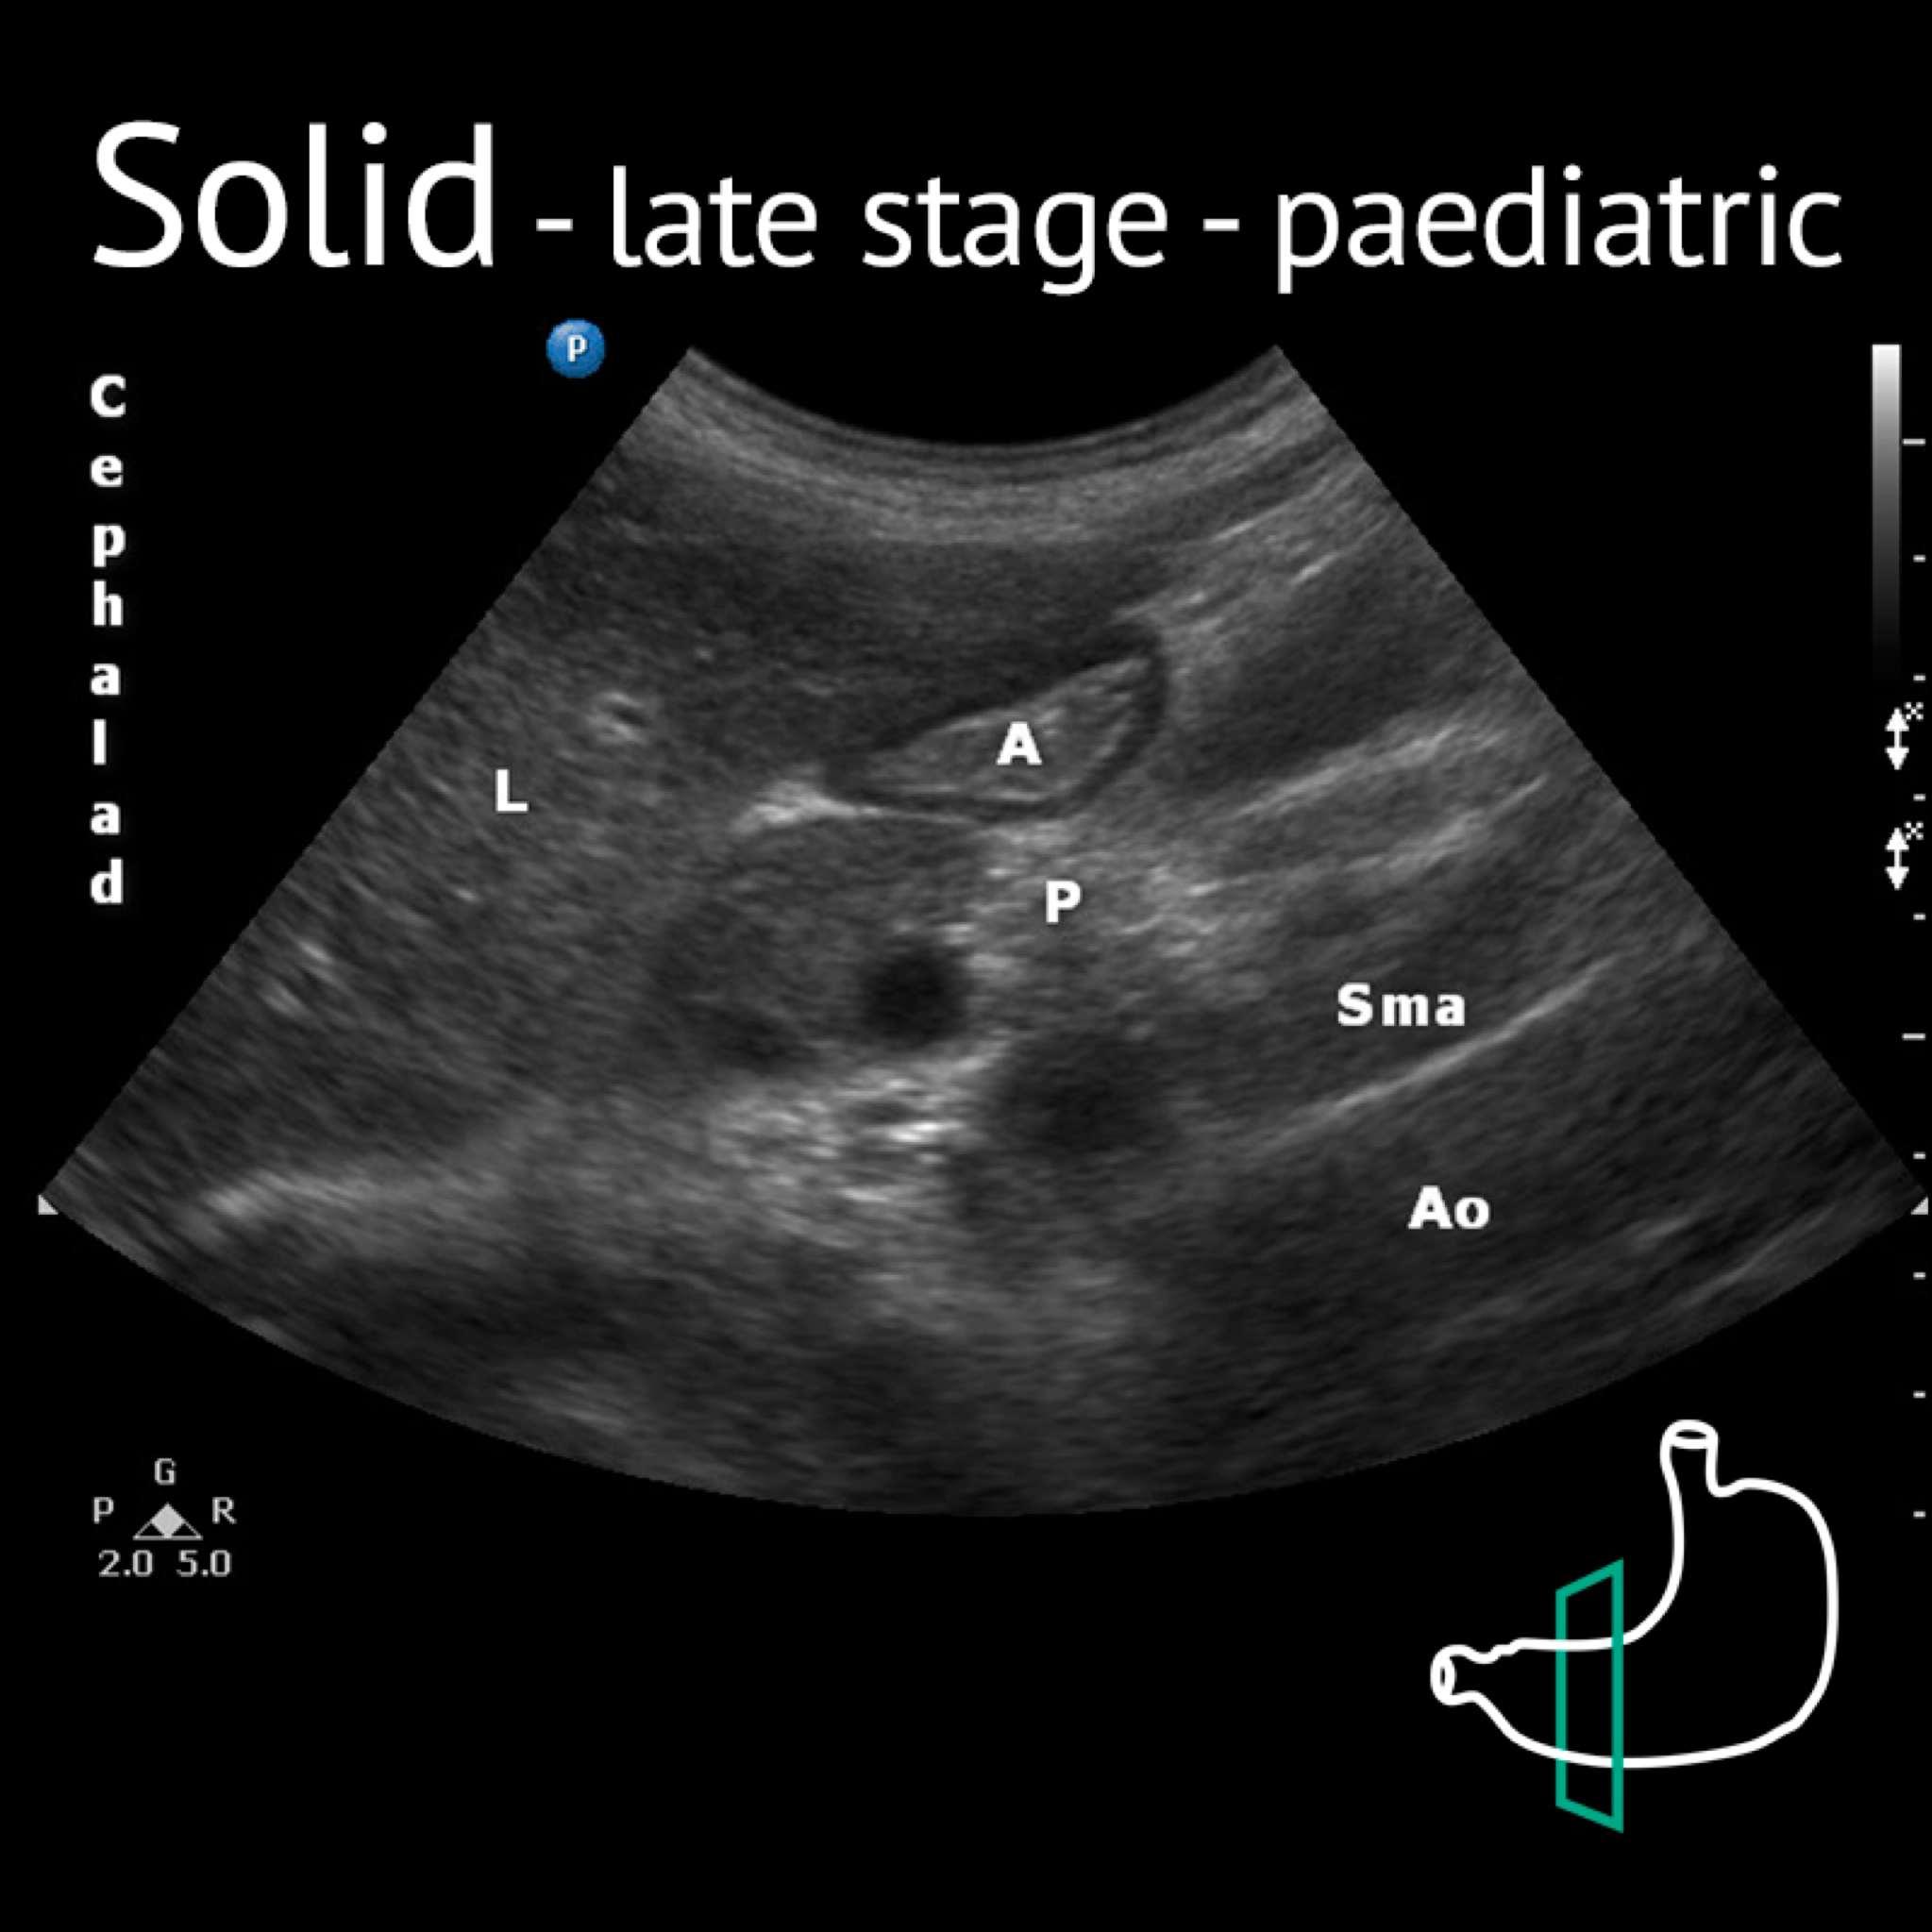

A: antrum; Ao: aorta; L: liver; P: pancreas; Sma: superior mesenteric artery; Sp: spine